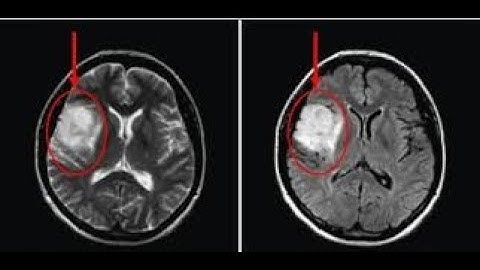

Brain Tumor Detection using Matlab - Image Processing + GUI step by step